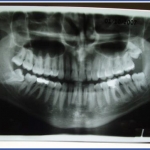

5.צילום פנורמי:

זהו צילום שנעשה במכון רנטגן ומכיל את שתי הלסתות ביחד. צילום פנורמי מראה לרופא את האנטומיה של הלסתות והשיניים בדו מימד. בצילום נראית האנטומיה של חלק מהגולגולת, החל ברצפת העין, מערות האף הלסתות, מפרקי הלסת ועוד.

הצילום נעשה בדרך כלל לפני עקירות שיני בינה- לצורך בדיקת קרבת השן לתעלת העצב, כמו כן לפני השתלות שיניים כאמצעי אבחנתי ראשוני הנותן לרופא מידע כללי לגבי מערות האף, גובה העצם ומיקום העצב. במקרים בהם קיימת פתולוגיה כלשהי (גידול, נגע, דלקת נרחבת) הצילום הוא אמצעי אבחנתי ראשוני מצויין.